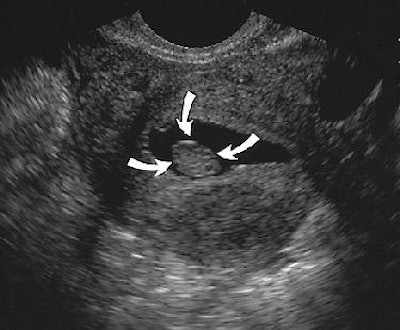

![]() |

| Same patient as above. Sonogram obtained after saline infusion shows homogeneous echogenic mass (arrows) in endometrial cavity, and no submucosal involvement by posterior uterine leiomyoma is present. Laifer-Narin S, Ragavendra N, Parmenter EK, Grant EG, "False-Normal Appearance of the Endometrium on Conventional Sonography: Comparison with Saline Hysterosonography," (AJR 2002; 178:129-133). |